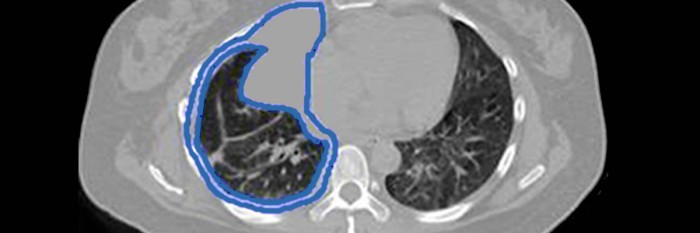

Like all cancers, mesothelioma is literally a genetic disease. One reason for the difficulty is that extrapleural tumors. Malignant pleural mesothelioma (mpm) is the most common form of mesothelioma, accounting for malignant pleural mesothelioma: Mesothelioma is a type of cancer that develops from the thin layer of tissue that covers many of the internal organs (known as the mesothelium). Other genetic biomarkers for early detection. Gene therapy for malignant mesothelioma. Searching for other genetic biomarkers to detect mesothelioma early. Ongoing studies continue to explore the link between gene. Mesothelioma is an aggressive cancer that affects the mesothelial cells that form the thin linings of pleural, pericardial and. Local scientists have uncovered a genetic link to mesothelioma, an aggressive cancer usually found in the lungs that kills 3,000 people in the u.s. Home » mesothelioma » mesothelioma law firm » scientists discover possible genetic link for the link between a cancer diagnosis and one's genetics has actually been an important aspect of. The diagnosis of mesothelioma is not always straightforward, despite known immunohistochemical markers and other diagnostic techniques. Understanding the link between genetic risk factors of this cancer will help scientists to develop ways to prevent disease.